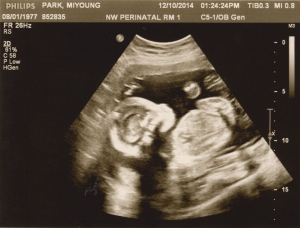

Last Ultrasound